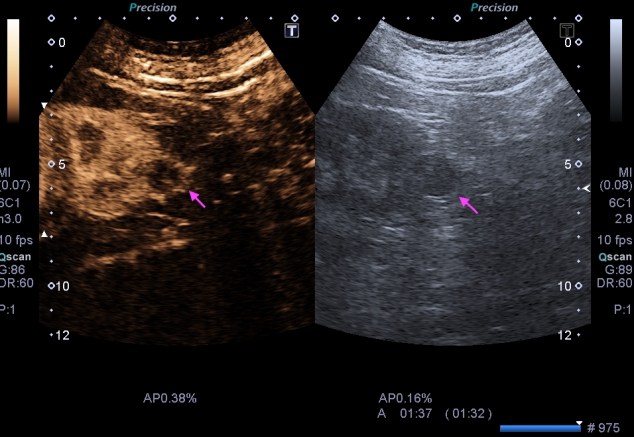

Quiero que te preguntes si sabrías diferenciar entre una imagen Doppler Color y una imagen en Modo Angio o Doppler Power. Vas a decir que sí, que lo sabes. Y es cierto, en la mayoría de las ocasiones distinguimos estas dos técnicas por el color, una rojo y azul, otra azul o morado, u otras coloraciones según la casa comercial.

Modo Doppler Color

Modo Angio o Doppler Power

Muy bien, en el Doppler Color (CDI) la magnitud de referencia que tomará nuestro equipo para hacer la medición de aquello que estemos interesados en estudiar será la longitud de onda. Sin embargo, en el Doppler Power o Modo Angio (Power) el equipo lee la Amplitud de la onda ultrasonográfica, la imagen de abajo.

Por tanto este modo de trabajo valoriza el movimientos de los hematíes, su velocidad, y la densidad de estas células sanguíneas las mide el modo angio, por eso el Doppler color se usa para flujos rápidos (medidad cuantitativa) y el modo angio para flujos lentos (medida cualitativa), por eso el modo angio es mas sensible, así que si eres muy sensible, eres modo angio… ¿lo entiendes?